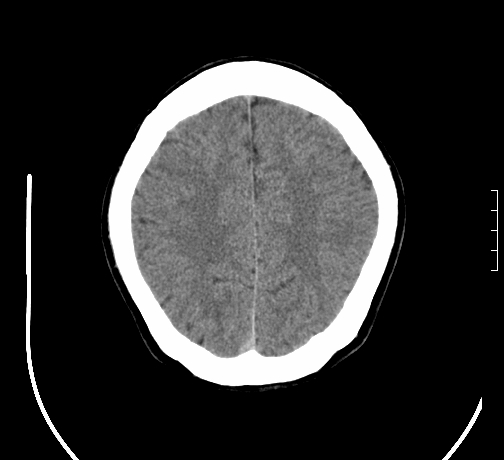

小脑发育畸形?

小脑萎缩。

考虑小脑发育不良,建议mri检查。

考虑小脑发育不良伴小脑萎缩,建议mri检查。

考虑小脑发育不良伴小脑萎缩,建议mri检查

考虑药物性小脑萎缩